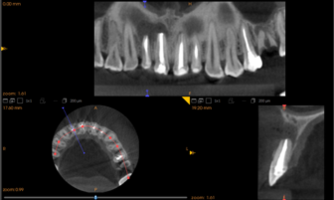

Компьютерная томография установила значительные различия в рентгеновской плотности остеопластических материалов «CrossBone»® и «Лиопласт»®.

Деминерализованная спонгиоза «Лиопласт»® является рентгенонегативной. Плотность материала, измеренная в первый день после операции РВК (209,08±25,1) оказалась намного меньше плотности здоровой костной ткани (391,25±28,83).

Это объясняется полной декальцинацией этого материала в процессе изготовления и отсутствием в нем минеральных компонентов (рис. 1).

Высокая плотность «CrossBone»® обусловлена наличием в его составе только неорганических компонентов (рис. 2).

Рис. 1. Гистограмма распределения плотности на дентальной компьютерной томографии фронтального отдела верхней челюсти пациентки О. непосредственно после операции РВК зуба 1.1, 1.2 с заполнением костной полости деминерализованной спонгиозой «Лиопласт»®.

Рис. 2. Гистограмма распределения плотности на дентальной компьютерной томографии фронтального отдела нижней челюсти пациента М. непосредственно после операции РВК зуба 4.1 с заполнением костной полости материалом «CrossBone»®.